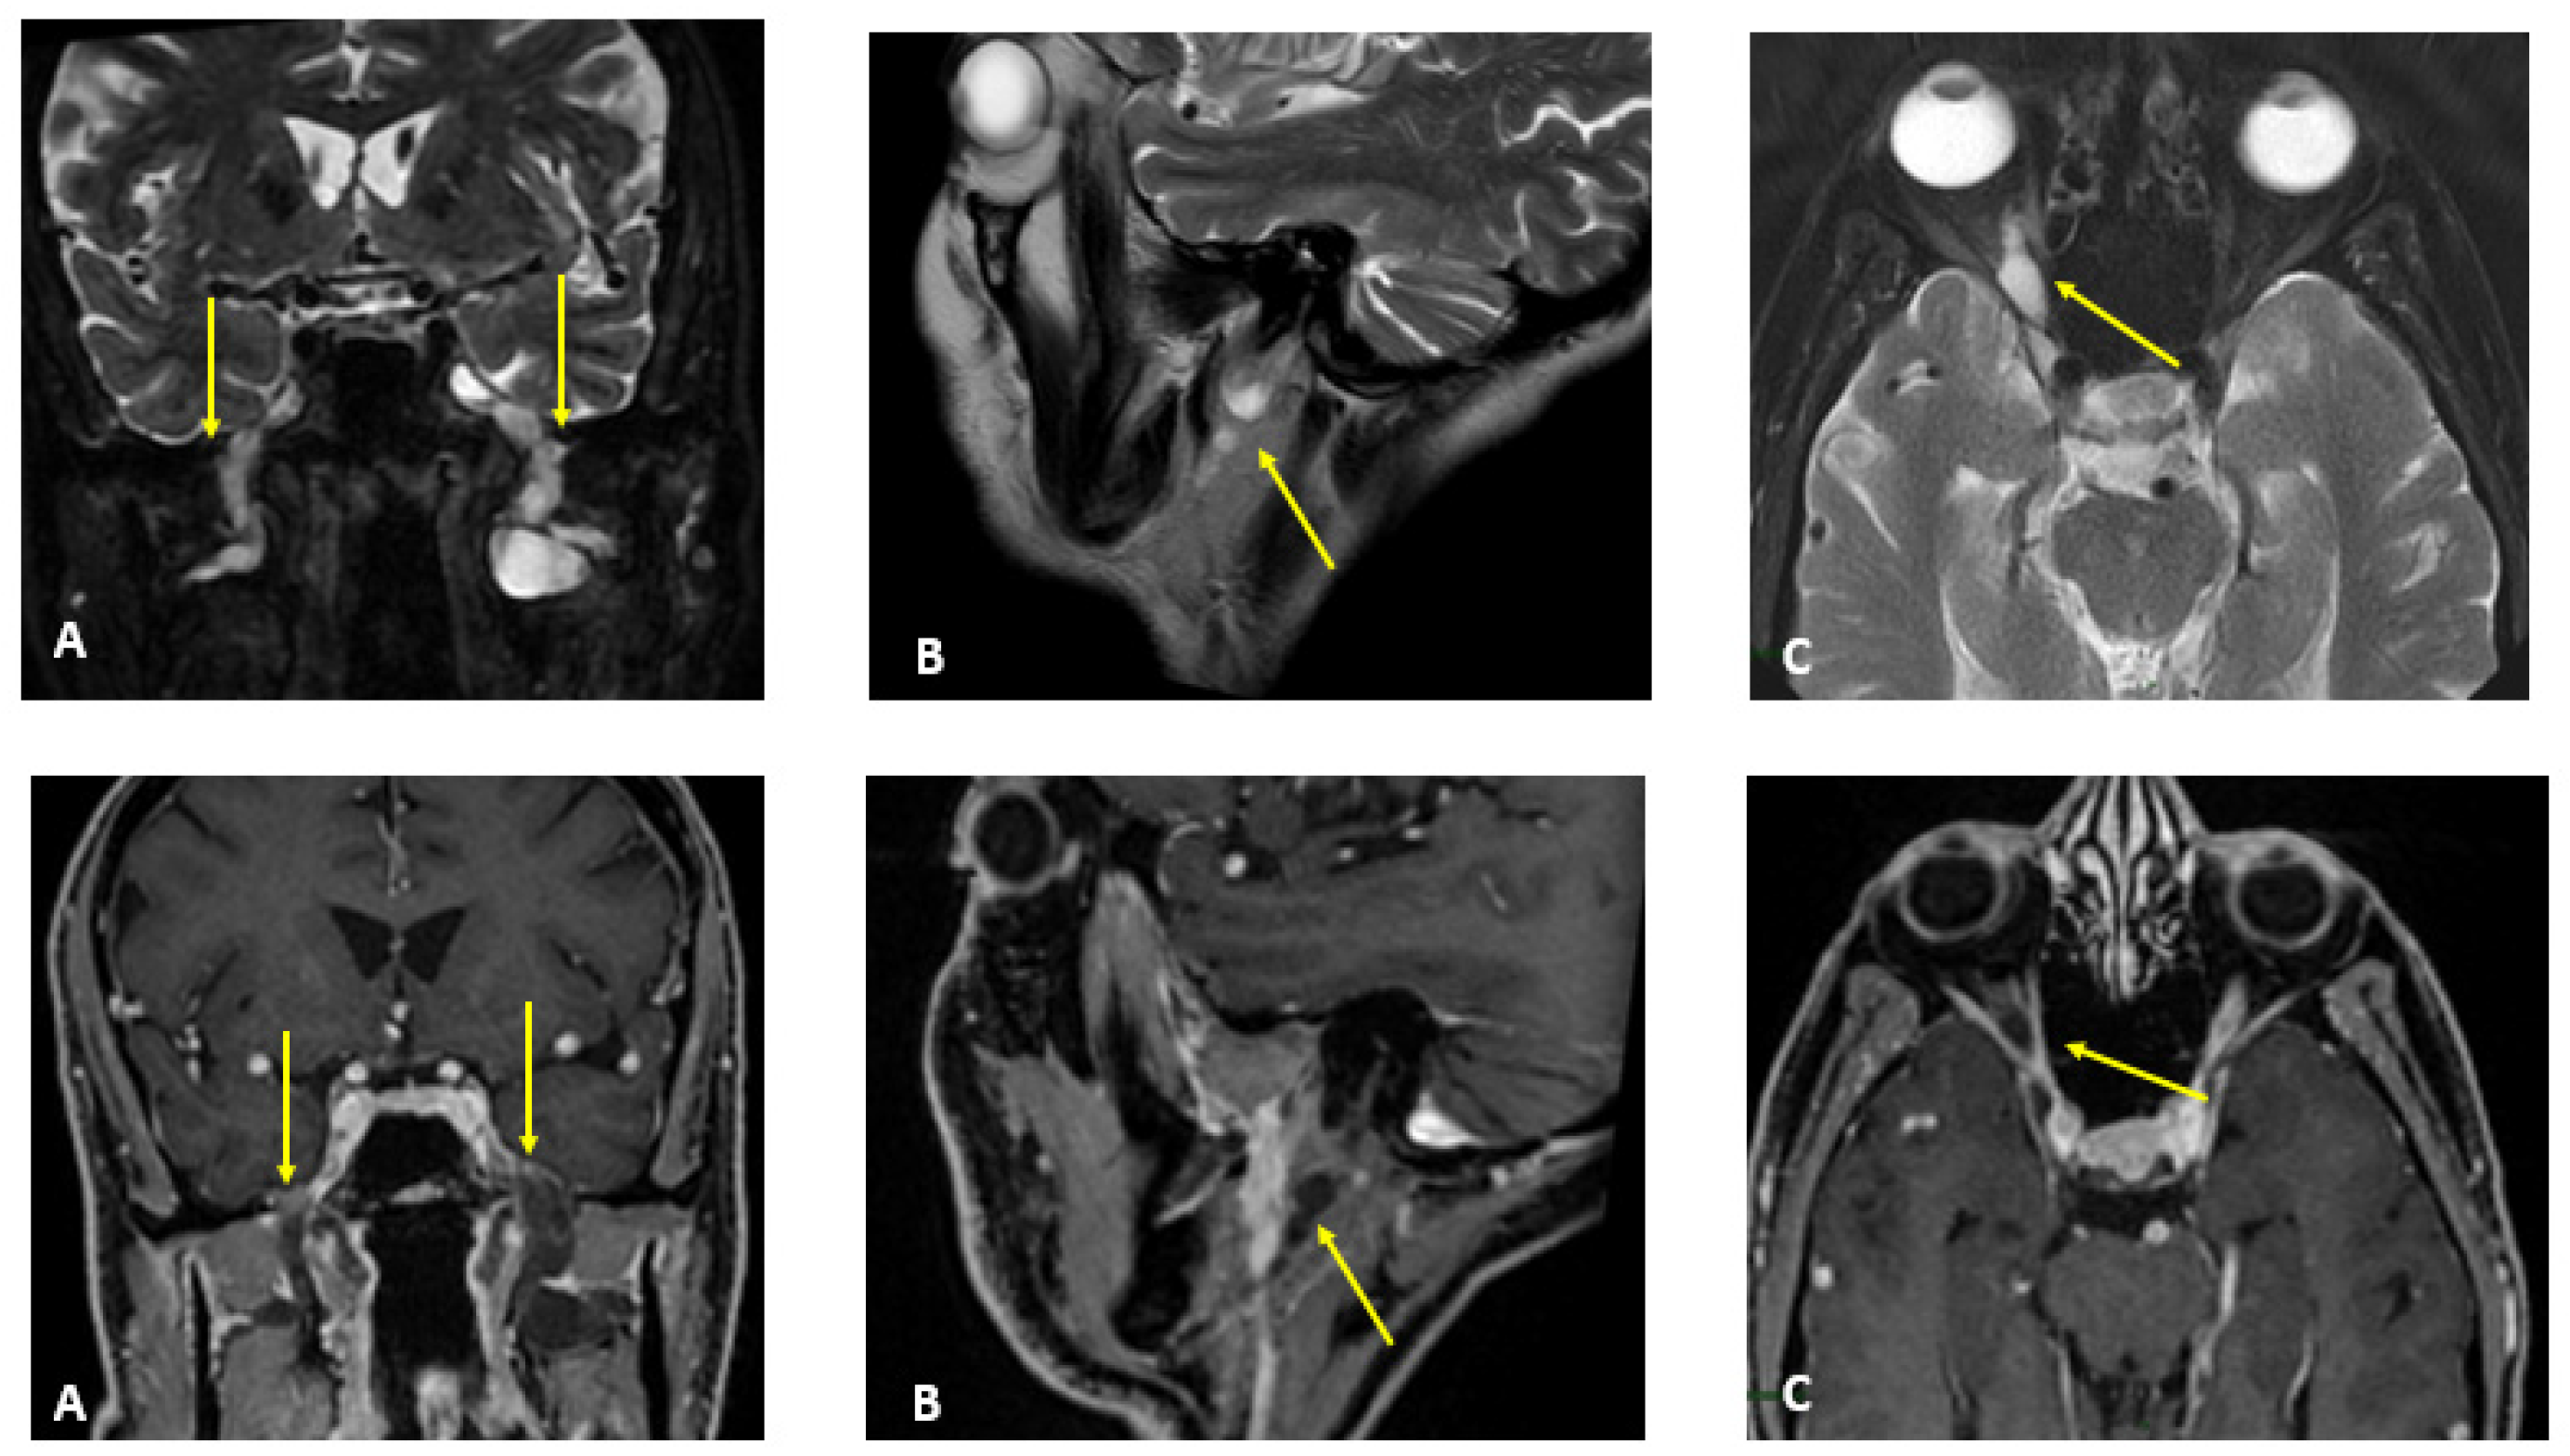

Figure 1.

MR T2-weighted (top) and T1-weighted fat post-contrast contrast images (bottom). The images in (A) are in the coronal plane, those in (B) are in the sagittal plane and those in (C) are in the axial plane. The images show thickened and pathological cranial nerves with a cystic appearance, high signals in T2w images and almost no contrast enhancement. In both (A), yellow arrows indicate pathological V3 branches of the trigeminal nerve (transverse diameter after the foramen ovale: left 3.8 mm; right 10 mm); in both (B), yellow arrows indicate pathological facial nerve in the intraparotid course (transverse diameter in intraparotid course: left 6.7 mm vs. right 2.2 mm); in both (C), yellow arrows indicate pathological right V1 branch of the trigeminal nerve (transverse diameter after superior orbital foramen: right 6.9 mm vs. left 2.3 mm).